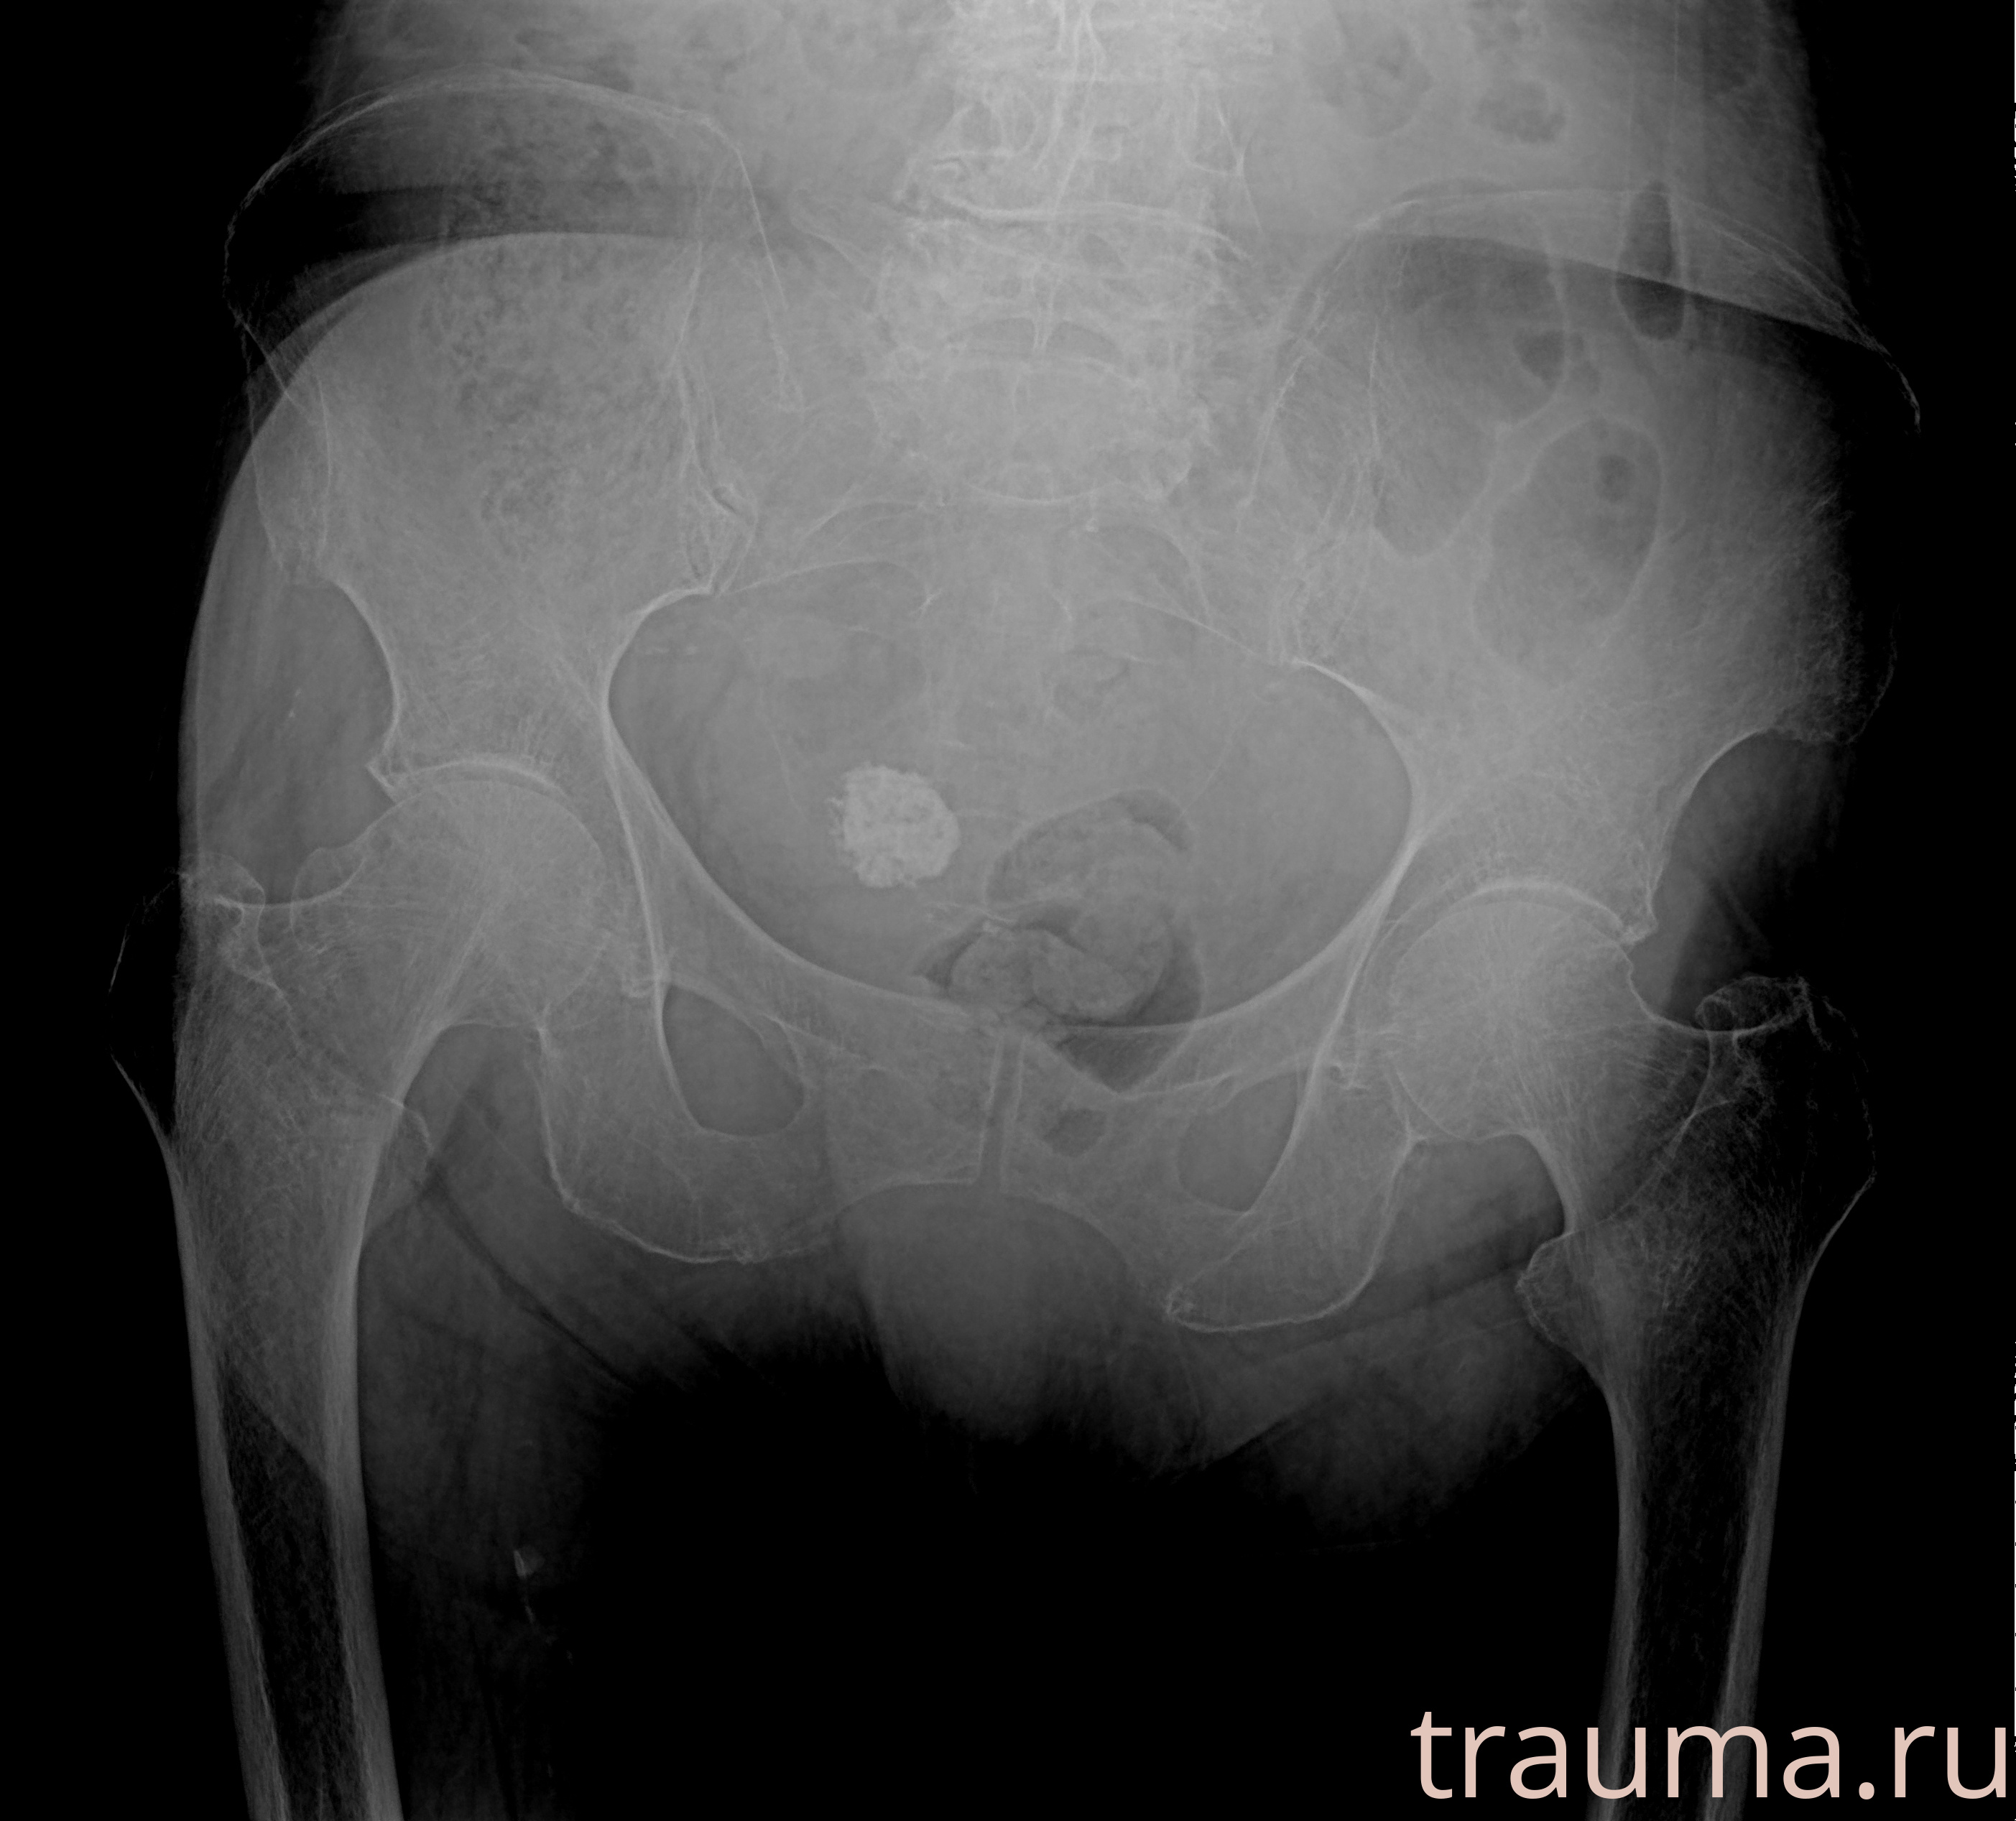

Рентген на дому: по вашему адресу приезжает врач-рентгенолог, травматолог-ортопед с мобильным рентгеновским аппаратом, проводит диагностику травмы или заболевания, делает необходимые рентгенограммы, дает рекомендации по дальнейшему лечению. Получить качественные снимки в домашних условиях возможно благодаря уникальной методике, разработанной МосРентген Центром для института  Склифосовского